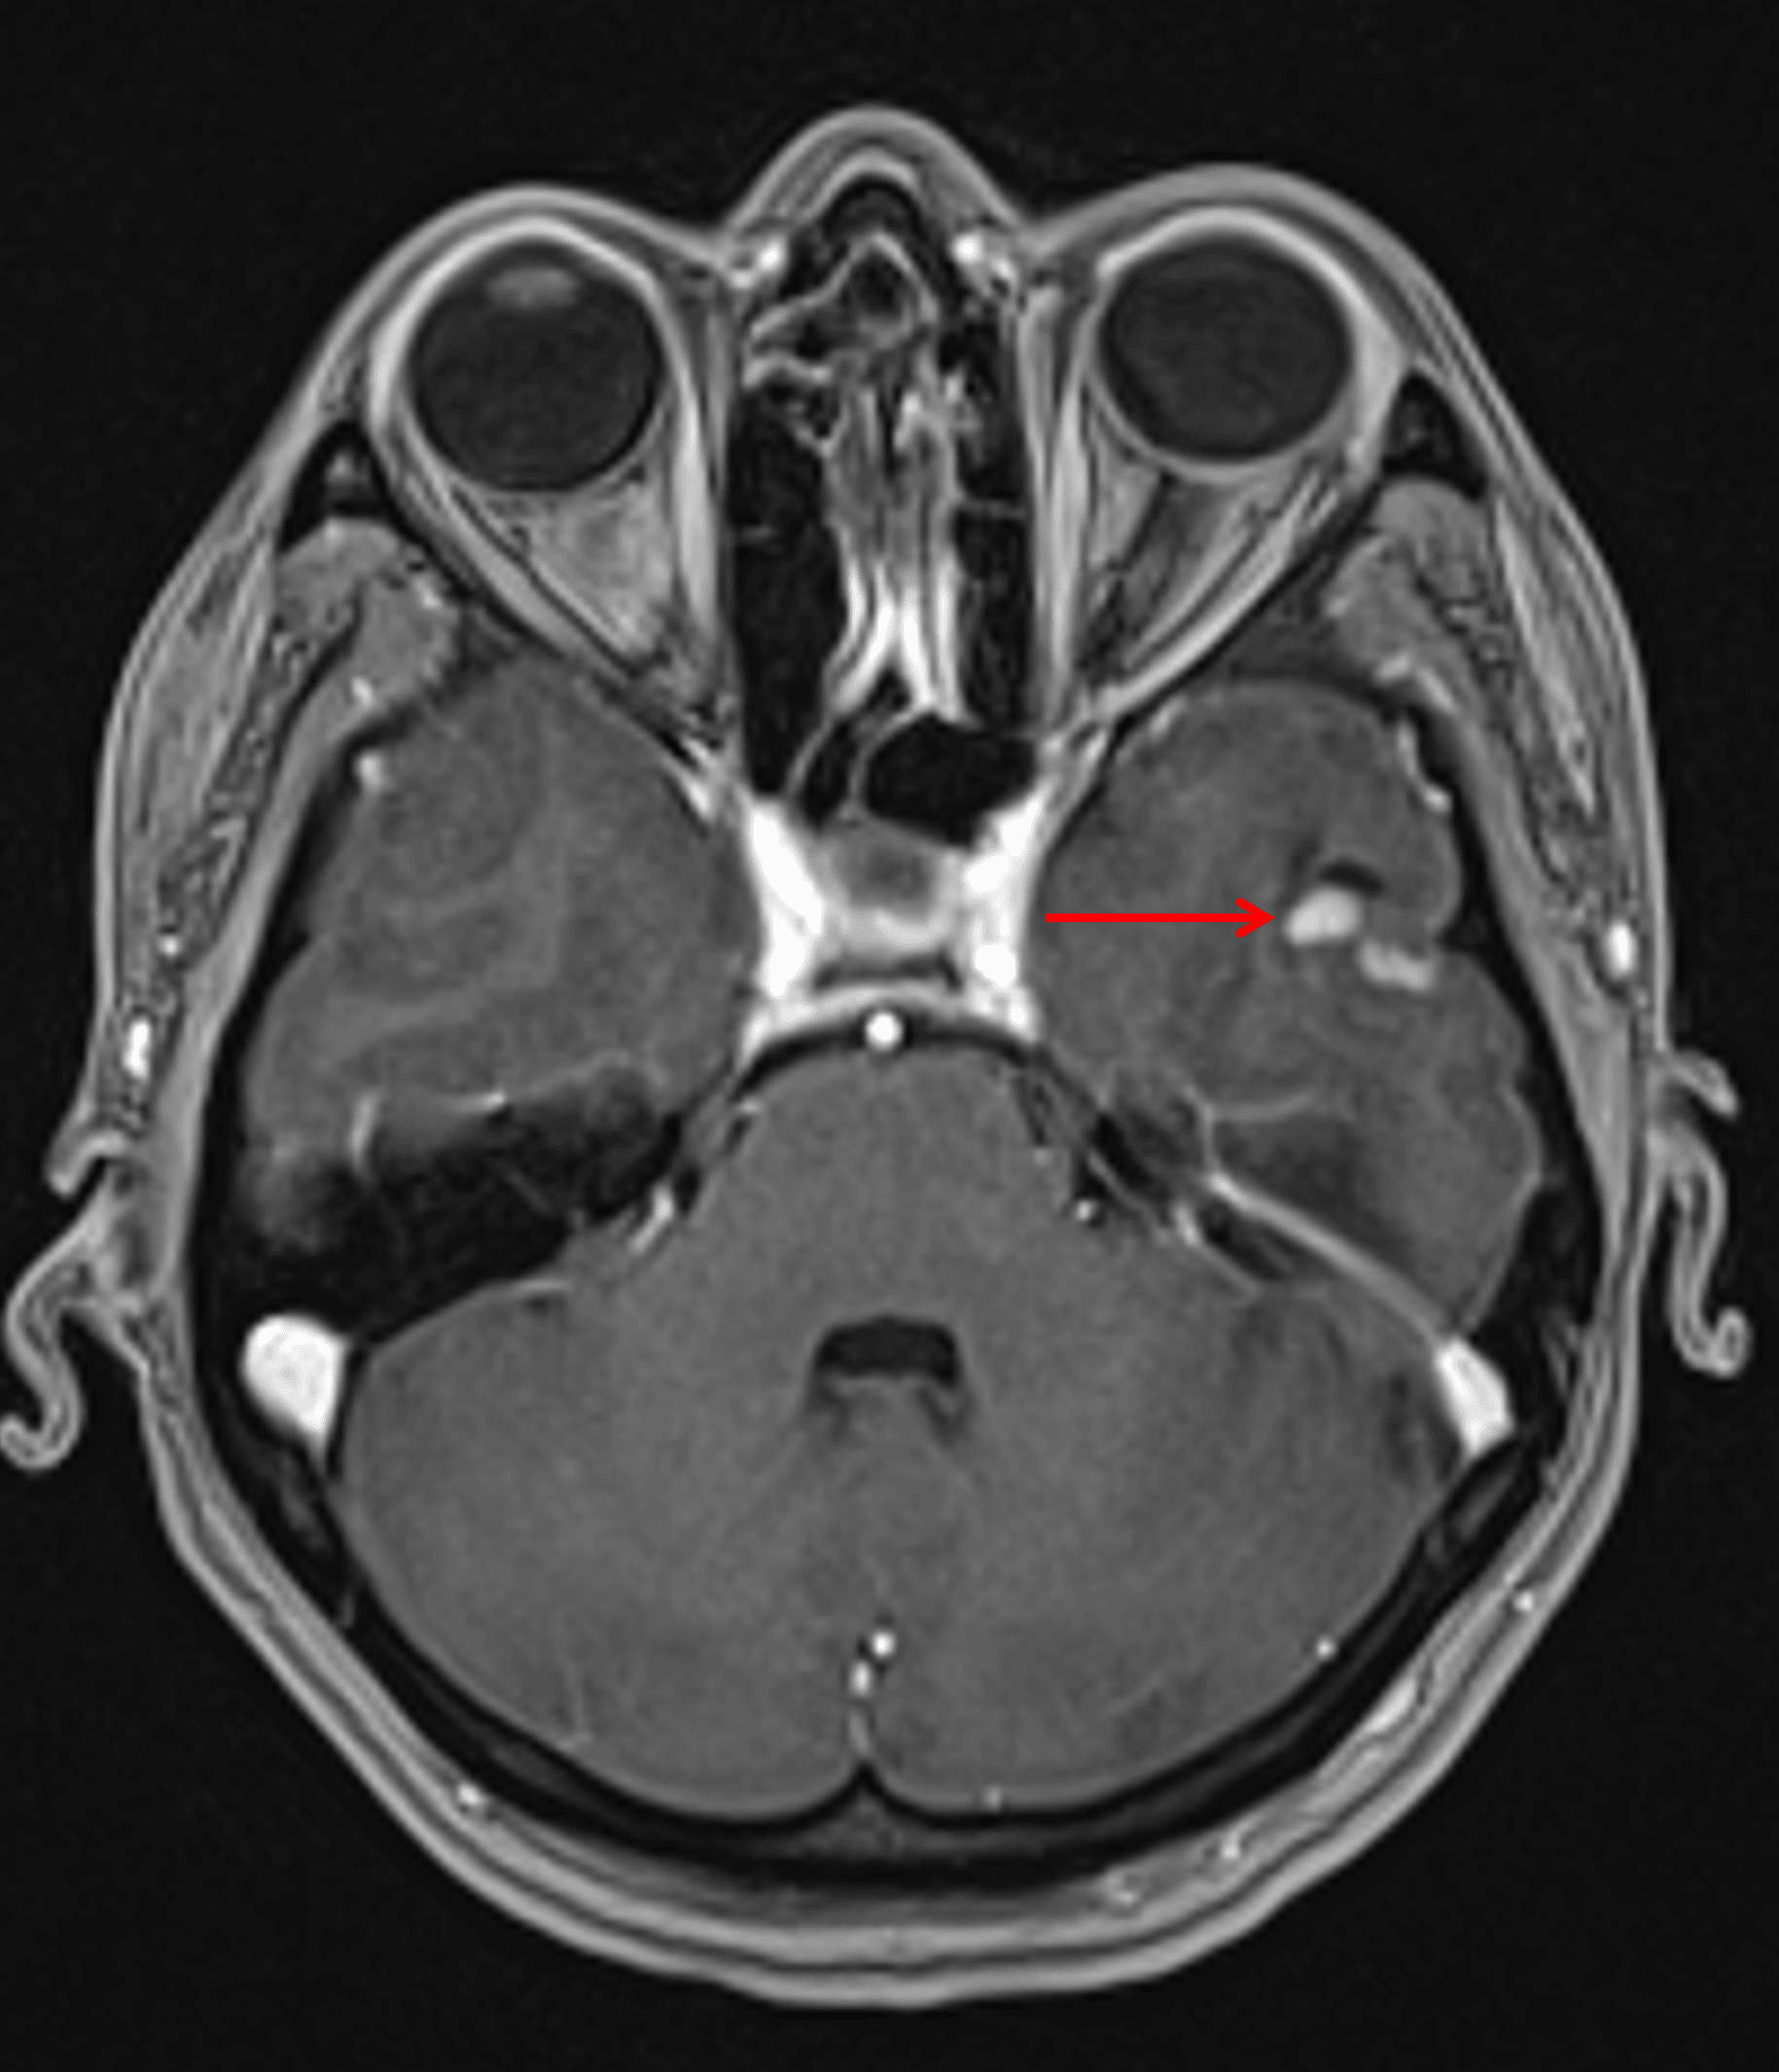

Small, mixed cystic and solid lesion in the inferior left temporal lobe with avid enhancement of the solid components (red arrow).

Minimal surrounding edema and mass effect (red arrow), which is typical for gangliogliomas.